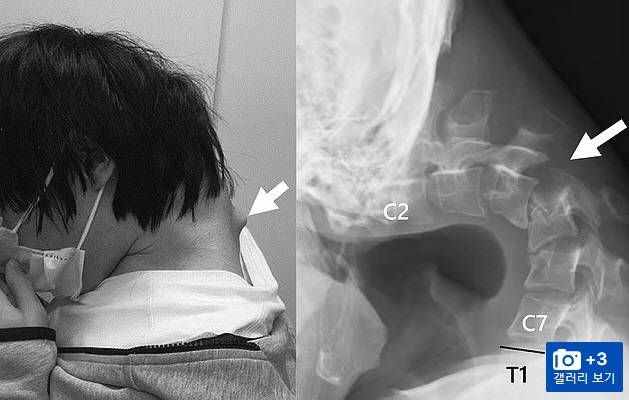

15일(현지시간) 영국 일간지 데일리메일에 따르면 일본의 한 병원 의료진은 휴대폰을 너무 많이 보다가 '머리떨어뜨림 증후군(드롭드 헤드 증후군 또는 플로피 헤드 증후군)'이 생긴 25세 남성 게이머의 사진을 공개했다.

사진을 보면 이 남성은 너무 약해진 목이 90도 가까이 꺾여 고개를 들게 없게 됐고, 음식을 심키는 데에도 문제를 겪었다. 이로 인해 식사량이 현저히 줄면서 심각한 체중 감소 증세를 보였다.

스캔 이미지에선 그의 목에서 돌출부가 튀어나온 것이 보인다. 의료진은 이 남성의 척추뼈가 부자연스런 자세를 오래 유지하면서 심하게 확장됐기 때문이라고 설명했다.

의료진은 "환자가 6개월 동안 심한 목 통증을 겪고 고개를 들 수 없게 된 후 도움을 요청했다"고 "스캔 결과, 시간이 지나면서 척추에 흉터와 같은 조직이 생겨 왜곡된 채 탈구된 것으로 나타났다"고 전했다.

의료진은 비수술적 교정 대신 수술을 결정했고, 먼저 척추뼈의 작은 부분과 목에 생긴 흉터 조직을 제거했다. 또 자세 교정을 위해 일련의 나사와 금속 막대를 목뼈에 삽입했다.

수술은 성공적이었다. 6개월 후 환자는 머리를 쉽게 수평 자세로 잡을 수 있게 됐고, 1년 후 추적 관찰 중에도 고개를 들고 음식을 삼키는 문제도 생기지 않았다.